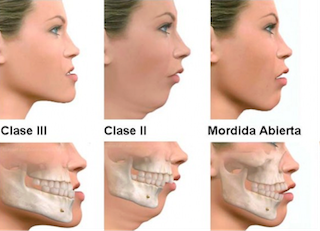

中でも「CT」や「セファロ」という口内のみではなく、顎をメインとしたレントゲンを撮ることで噛み合わせをきちんと考慮した矯正を行うことが可能になります。